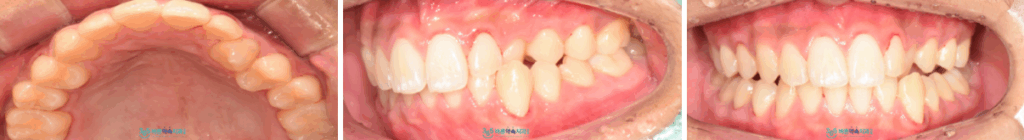

먼저 구강 내를

확인해 보았더니

위턱 왼쪽 송곳니가

아래턱 송곳니 보다

안쪽으로 밀려 들어가 있는 상태였으며

이로 인해 어금니가 안정적인 교합이

이루어지지 않고 있었습니다.